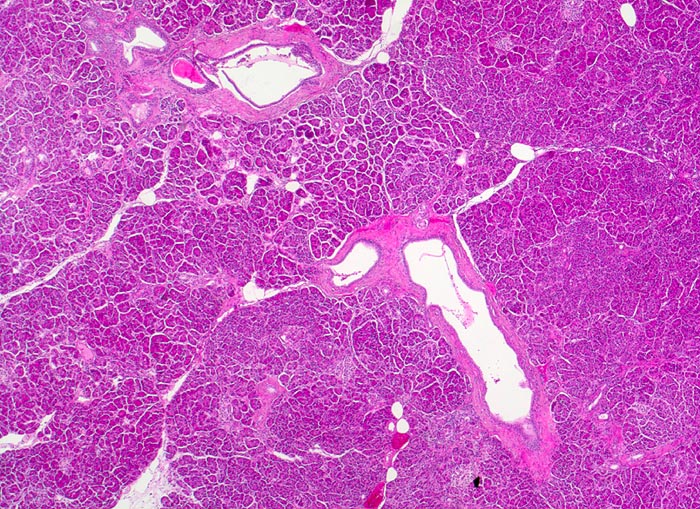

Normales exokrines Pankreas

Das Pankreas ist von einer dünnen Kapsel umgeben, von der aus schmale bindegewebige Septen in das Parenchym eindringen und zu einer Lobulierung führen. In den Septen verlaufen die Ausführgänge des exokrinen Pankreas. Die einzelnen Läppchen bestehen aus mehreren Azini (=mehrere Azinuszellen gruppiert um zentroazinäre Zellen überleitend in ein Schaltstück).

Histologie

25